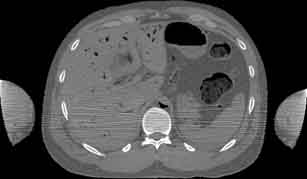

Visible Human male: Sectio transversalis 1535

CT

NMR

Pd                          / T2 \                         T1